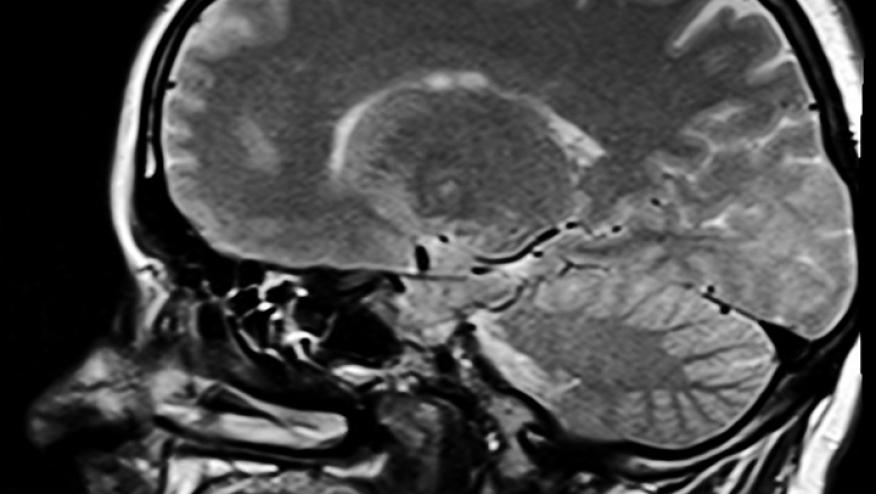

The neurologic outcomes of interest were defined as a diagnosis of a central demyelinating disease, which includes multiple sclerosis, optic neuritis, transverse myelitis, and other central demyelinating diseases. Patients with a history of demyelinating diseases and those taking TNFi prior to 1999 or prior to IBD diagnosis were excluded.